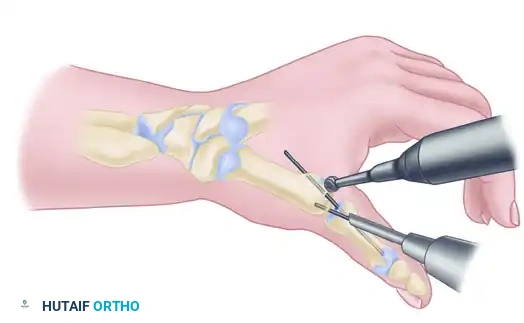

3. Provisional Fixation and Bone Grafting

Place the thumb in the optimal position (45 degrees palmar abduction, slight pronation). Temporarily stabilize the joint by driving a 1.6-mm Kirschner wire (K-wire) antegrade from the dorsal metacarpal shaft into the trapezium.

Confirm bony apposition, alignment, and hardware placement with multi-planar fluoroscopy.

Option B: Kirschner Wire Fixation

If K-wire fixation is chosen (often preferred in cases of small trapezial bone stock where a plate might cause comminution), drive three 1.1-mm or 1.6-mm wires retrograde from the metacarpal into the trapezium.

The first pin follows the planned longitudinal axis of the bone fusion. The other two pins should diverge 10 to 20 degrees from this central axis to provide rotational stability.

Take care to avoid pin penetration into the scaphotrapeziotrapezoid (STT) joint. Leave the pins protruding slightly outside the skin, capped, for later removal in the clinic.